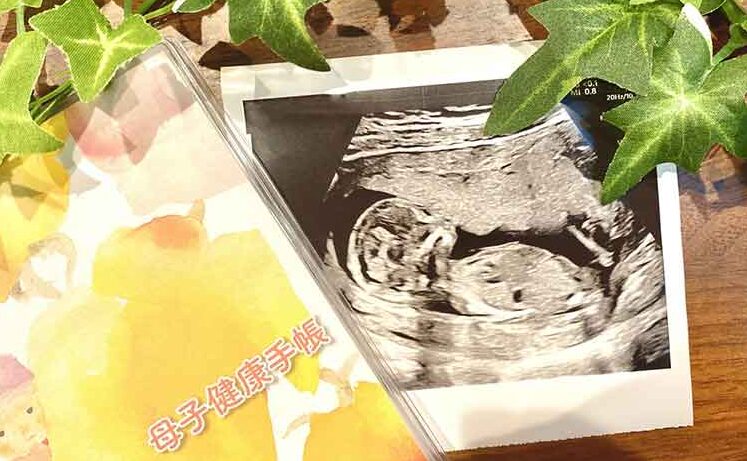

母子健康手帳は、私たちが子どもを育てる上で欠かせない大切なツールです。この手帳は、妊娠から出産、そして子どもの成長に至るまでの健康管理をサポートします。私たちがこの手帳を使うことで、医療機関とのコミュニケーションが円滑になり、必要な情報を簡単に把握できます。

母子健康手帳は、妊娠から子どもの成長までの健康を管理するための重要なツールです。この手帳は、妊婦や育児中の家庭に必要な情報を提供します。

母子健康手帳には、妊娠から出産、子どもの成長に関する様々な情報が含まれています。この手帳によって、母子の健康管理が効率化されます。